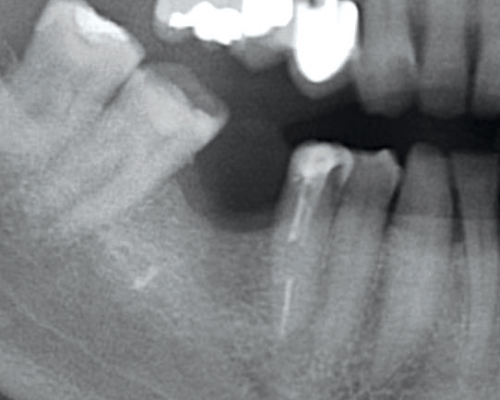

01/07 - Situation before tooth extraction.Socket preservation with permamem® - Dr. M. Turco

Initial panoramic x-ray with failing tooth 16